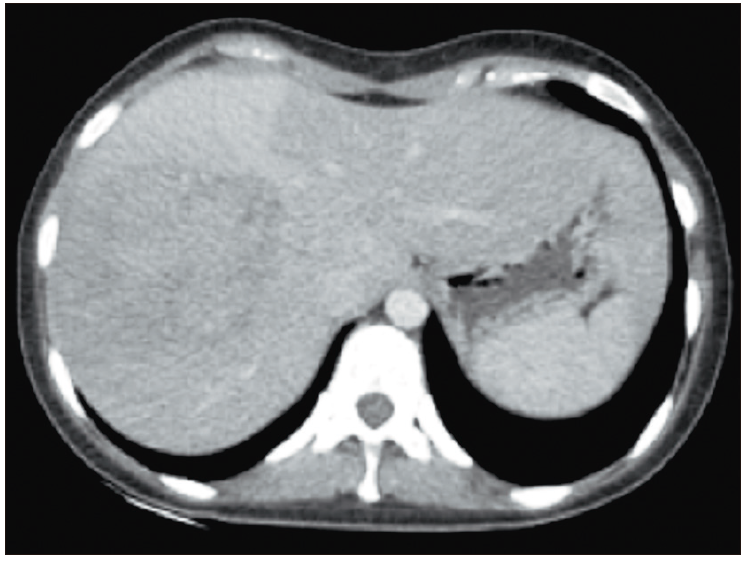

Se realiza una tomografía de tórax, abdomen y pelvis con contraste oral y endovenoso (Figura 1), en la que se observa una formación voluminosa de 9 cm, de contornos lobulados, heterogénea y con área central hiperdensa. Se prosigue a realizar una resonancia de abdomen trifásica, en la cual se observa una lesión sólida de contornos irregulares y señal heterogénea de 55 x 56 x 50 mm, hipervascular, con realce capsular periférico tardío, múltiples imágenes nodulares satélites y trombosis de la vena porta derecha (Figuras 2a, 2b y 2c).

Figura 1. Imagen axial de TC con contraste endovenoso, obtenida en

fase venosa portal, que muestra la presencia de una masa en el lóbulo hepático derecho que tiene bordes

parcialmente definidos y un escaso refuerzo central. La lesión es ligeramente heterogénea